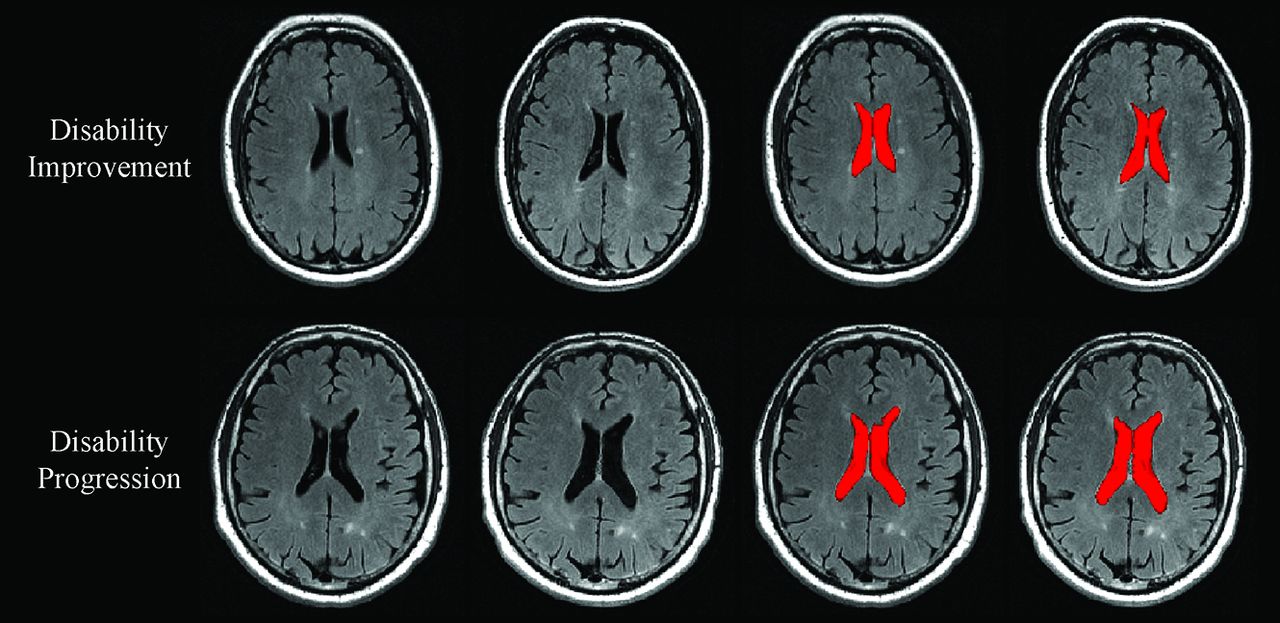

On-line Table 2 shows PLVVC and PBVC in disability progression, disability improvement, and stable groups. Figures 1 and 2 show representative changes of PLVVC and PBVC in disability progression and disability improvement in individual patients during follow-up, respectively. At baseline, there were no significant LVV and whole-brain volume differences among patients with MS in the disability progression, disability improvement, and stable groups.

Change in lateral ventricle volume in patients with MS disability progression and disability improvement. In the upper and lower rows are shown in patients with MS with disability improvement and disability progression, respectively. From left to right are baseline and followup T2-FLAIR images and images of NeuroSTREAM LVV (highlighted in red) segmentation at baseline and at follow-up. Please note higher annualized percentage LVV change in patients with MS with disability progression (5.7%) compared with disability improvement (1.1%).

During the follow-up period, the annualized PLVVC was 1.6% ± 2.7% in disability improvement, 2.1% ± 3.7% in stable status, and 4.1% ± 5.5% in disability progression groups (adjusted P < .001). Both disability improvement and stable groups had significantly lower total and annualized PLVVC compared with the disability progression group (adjusted P < .001). The disability improvement group did not show a significant difference in total (adjusted P = .6) or annualized (adjusted P = .92) PLVVC compared with the stable group. The estimated means and 95% confidence intervals for the analyses are shown in On-line Table 3.